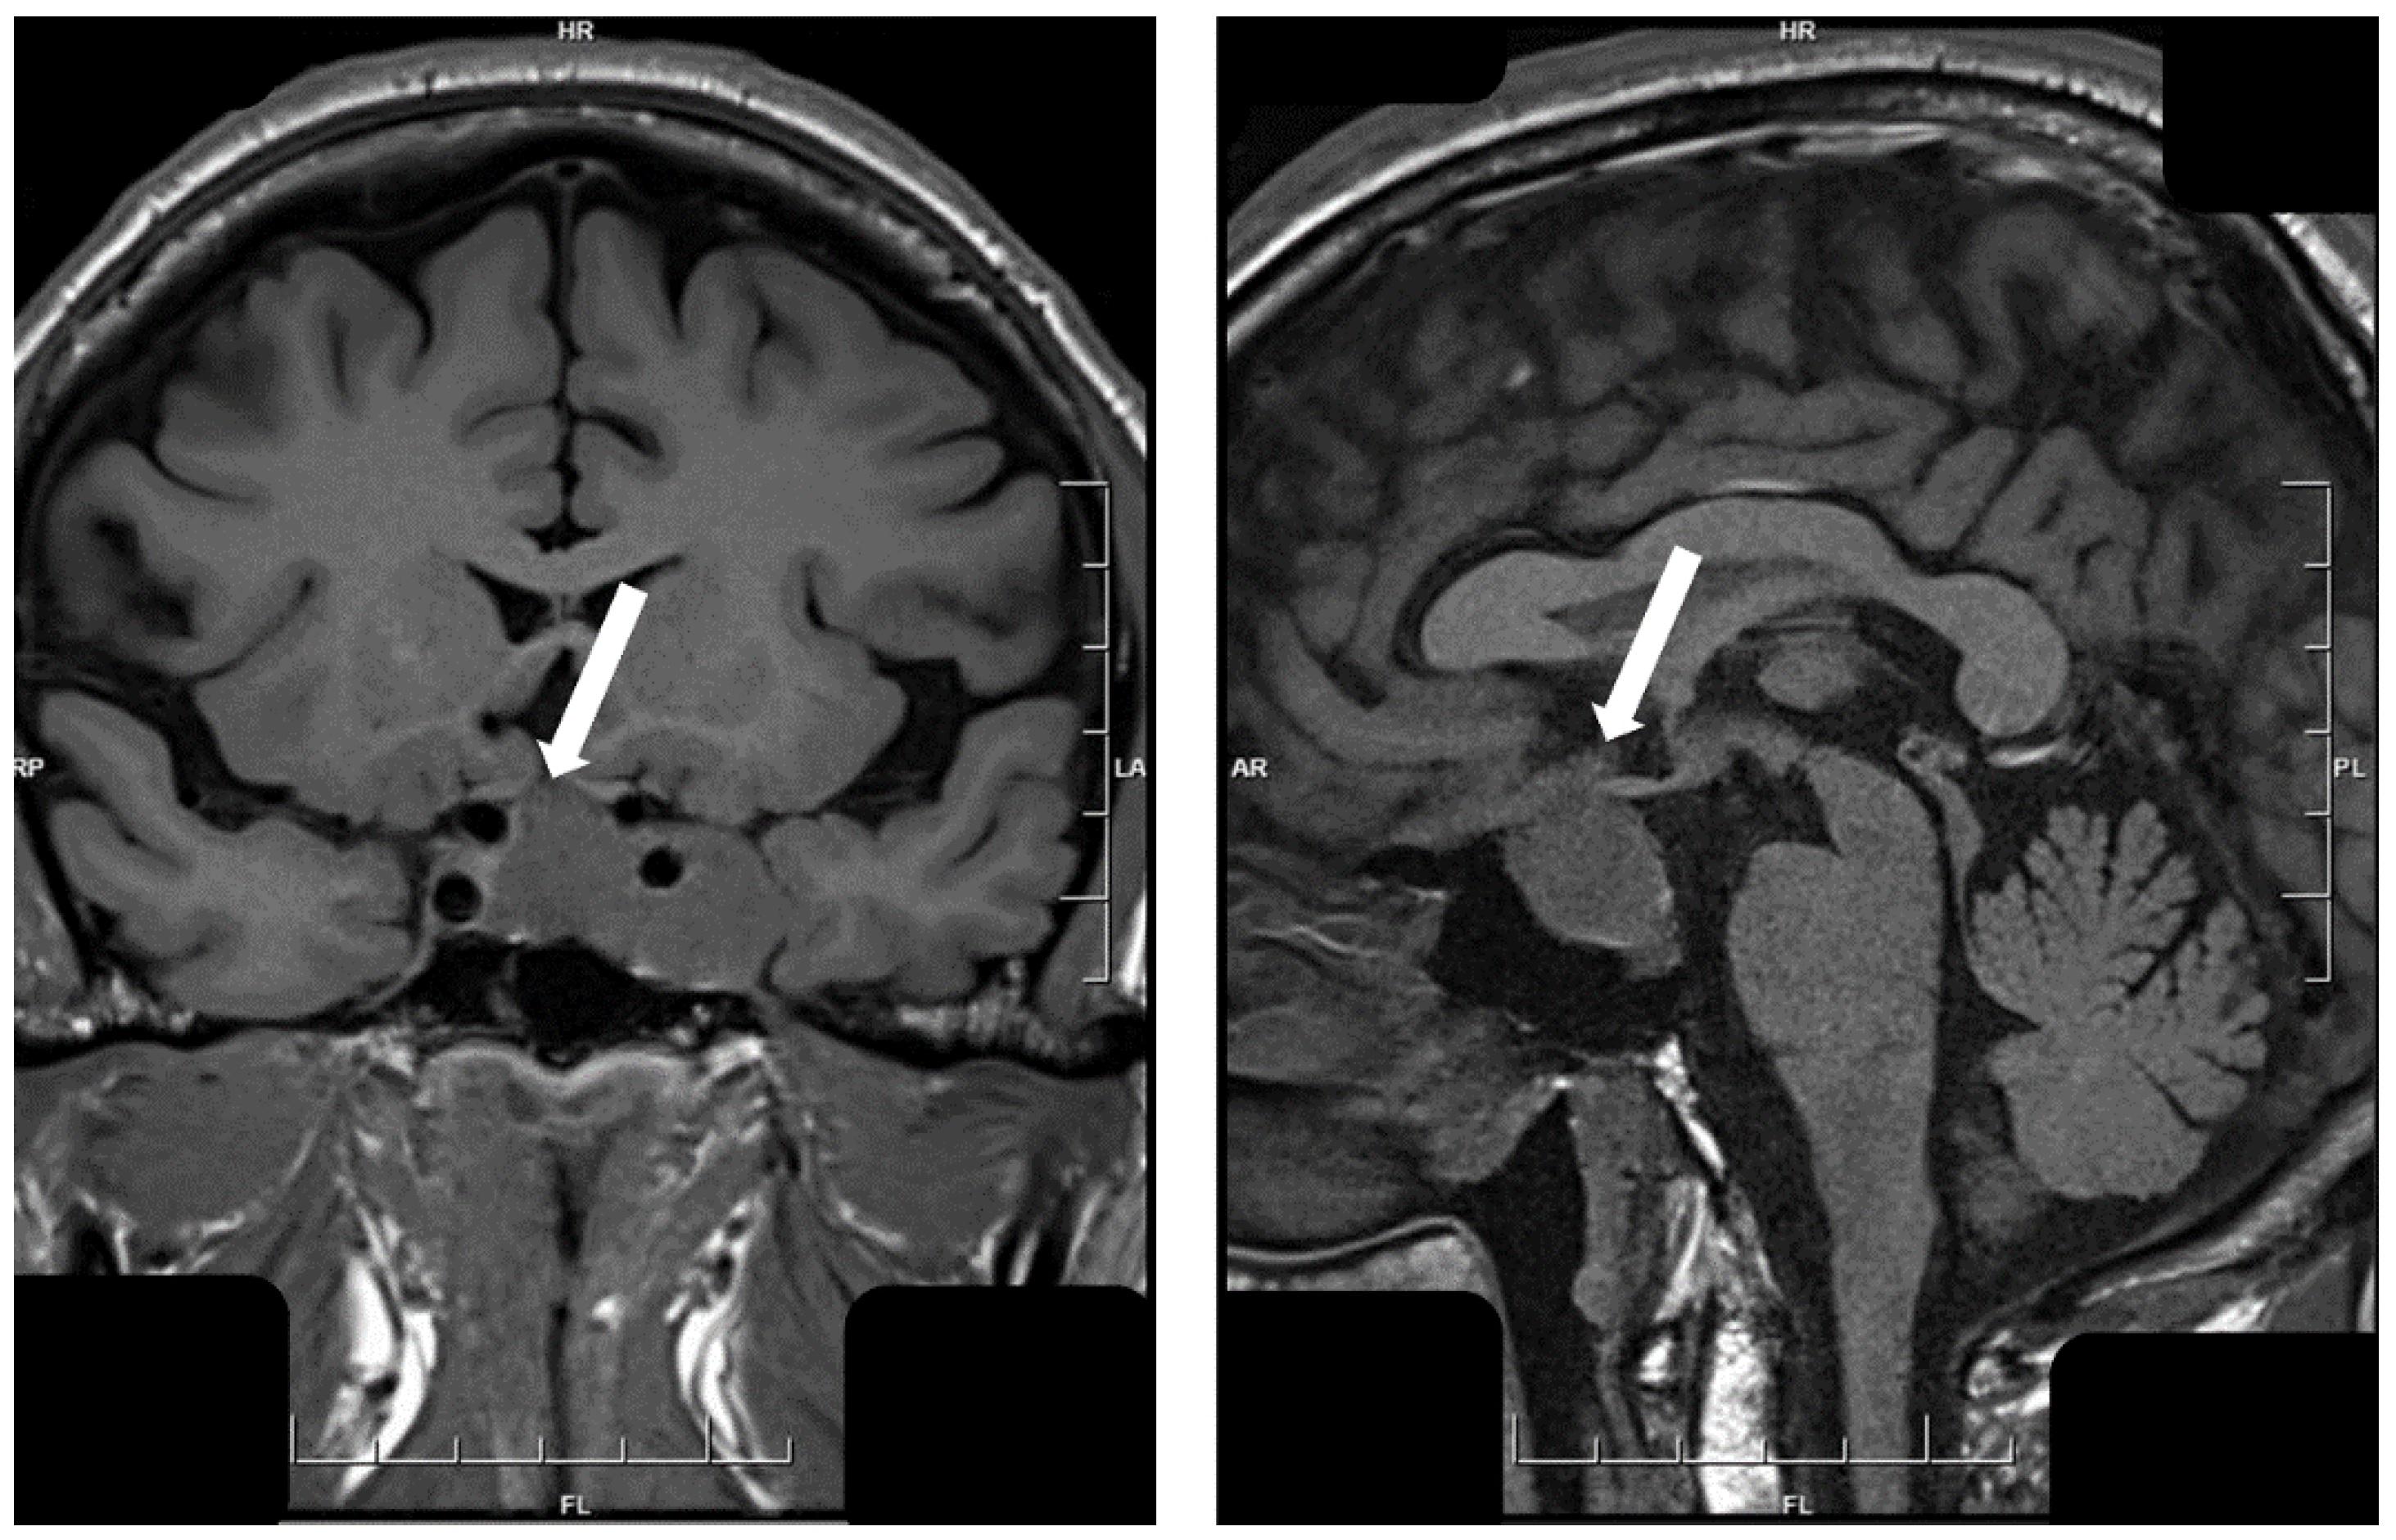

手腳異常腫大或臉形改變可別大意,可能是肢端肥大症惹禍,尤其早期症狀表現不明顯且病程緩慢,導致許多患者誤以為是正常老化,後續可能衍生包括心臟肥厚、心臟衰竭或肝臟肥厚、骨骼軟組織增生肥大等問題;臺大醫院內科部副主任暨代謝內分泌科主任王治元教授指出,肢端肥大症大多是因為腦下垂體分泌過多生長激素所造成,若發生在成年人身上,因生長板已閉合,就會造成骨骼異常增生,像下巴或前額突出、牙齒裂開等現象,可透過抽血做初步的篩檢。

治療上,主要針對減少生長激素產生為目的,基本上會優先評估患者是否適合以手術切除腫瘤,再輔以加馬刀、電腦刀等放射治療,透過局部定位治療病灶,但放射治療腦下垂腫瘤得經若干年後,腫瘤才會逐漸消失,若治療仍不理想,則須以口服藥或注射藥物治療加以輔助;王治元教授補充,早期即已有所謂體抑素抑制劑等治療方式,但患者需每天打三針且疼痛感較高,直到近年來出現長效型注射凝膠劑,患者只需一個月打一針即可。

治療上,主要針對減少生長激素產生為目的,基本上會優先評估患者是否適合以手術切除造成此症的腫瘤,再輔以加馬刀、電腦刀等放射治療。